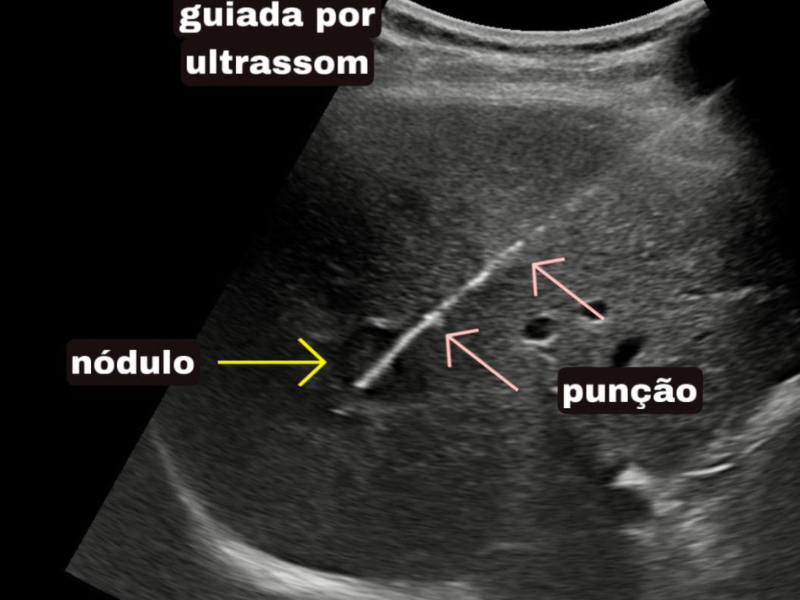

Conquistou o primeiro lugar no exame nacional da SOBRICE e se destaca em procedimentos minimamente invasivos, como ablação de tumores e biópsias guiadas. Atende nos melhores hospitais de São Paulo, incluindo o Hospital Nove de Julho e Vila Nova Star.